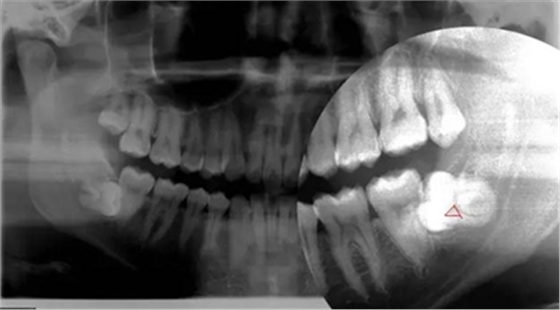

智齒水平阻生(長橫過來了),影響前面牙齒或者致前面牙齒擁擠不齊

1.水平阻生影響前牙